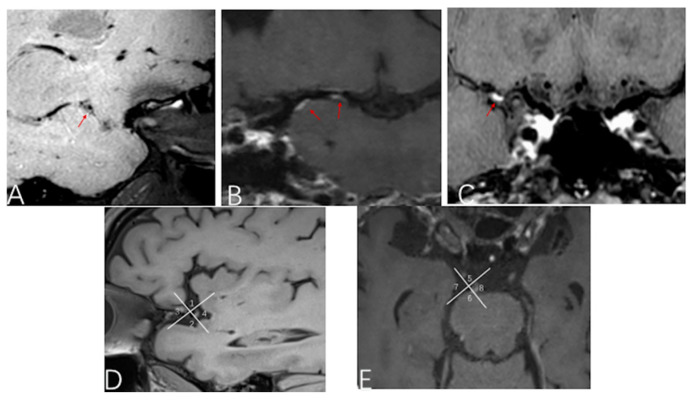

Background: Intracranial atherosclerosis disease (ICAD) represents a significant etiology of stroke. This study aimed to evaluate correlations between intracranial atherosclerotic burden and risk of ischemic events. Methods: In this prospective observational study, all enrolled patients underwent High-Resolution Magnetic Resonance vessel wall Imaging (HR MR-VMI) within two weeks of onset, or of enrollment. Baseline assessments included modified American Heart Association plaque type, stenosis degree, intra-plaque hemorrhage (IPH), plaque thickness, plaque length, and vessel wall enhancement. Modified Rankin Scale (mRS) was followed with one-year treatment in adherence to the guidelines. Comparative analyses were conducted between symptomatic and asymptomatic groups, culprit versus non-culprit plaques, and favorable versus poor prognosis groups. Results: The study included 129 symptomatic and 42 asymptomatic patients. Hypertension, diabetes, and smoking were more prevalent in patients in the symptomatic group. Vulnerable plaque (97.7% vs. 64.3%, p = 0.003), IPH (17.8% vs. 4.8%, p = 0.022) and higher stenosis degree (χ2 = 2.675, p = 0.008) were significantly more prevalent in the symptomatic group. Culprit plaques were predominantly located in the superior wall of the middle cerebral artery (MCA) (χ2 = 15.561, p = 0.001) and the left wall of the basilar artery (χ2 = 34.138, p = 0.008). Factors associated with poor prognosis included older age (63.63 ± 8.19 vs. 55.63 ± 13.15, p = 0.001), presence of IPH (31.82% vs. 14.29%, p = 0.037), and elevated D-dimer levels (0.77 ± 0.60 vs. 0.40 ± 0.36, p = 0.022). Conclusions: Vulnerable plaque, specific lesion locations, and higher stenosis degree are significantly associated with ischemic events in ICAD. While plaque enhancement and stenosis correlate with stroke occurrence, they show no clear association with prognosis. Neither the length nor the thickness of plaques manifests a significant correlation with either stroke events or the prognostic outcomes.